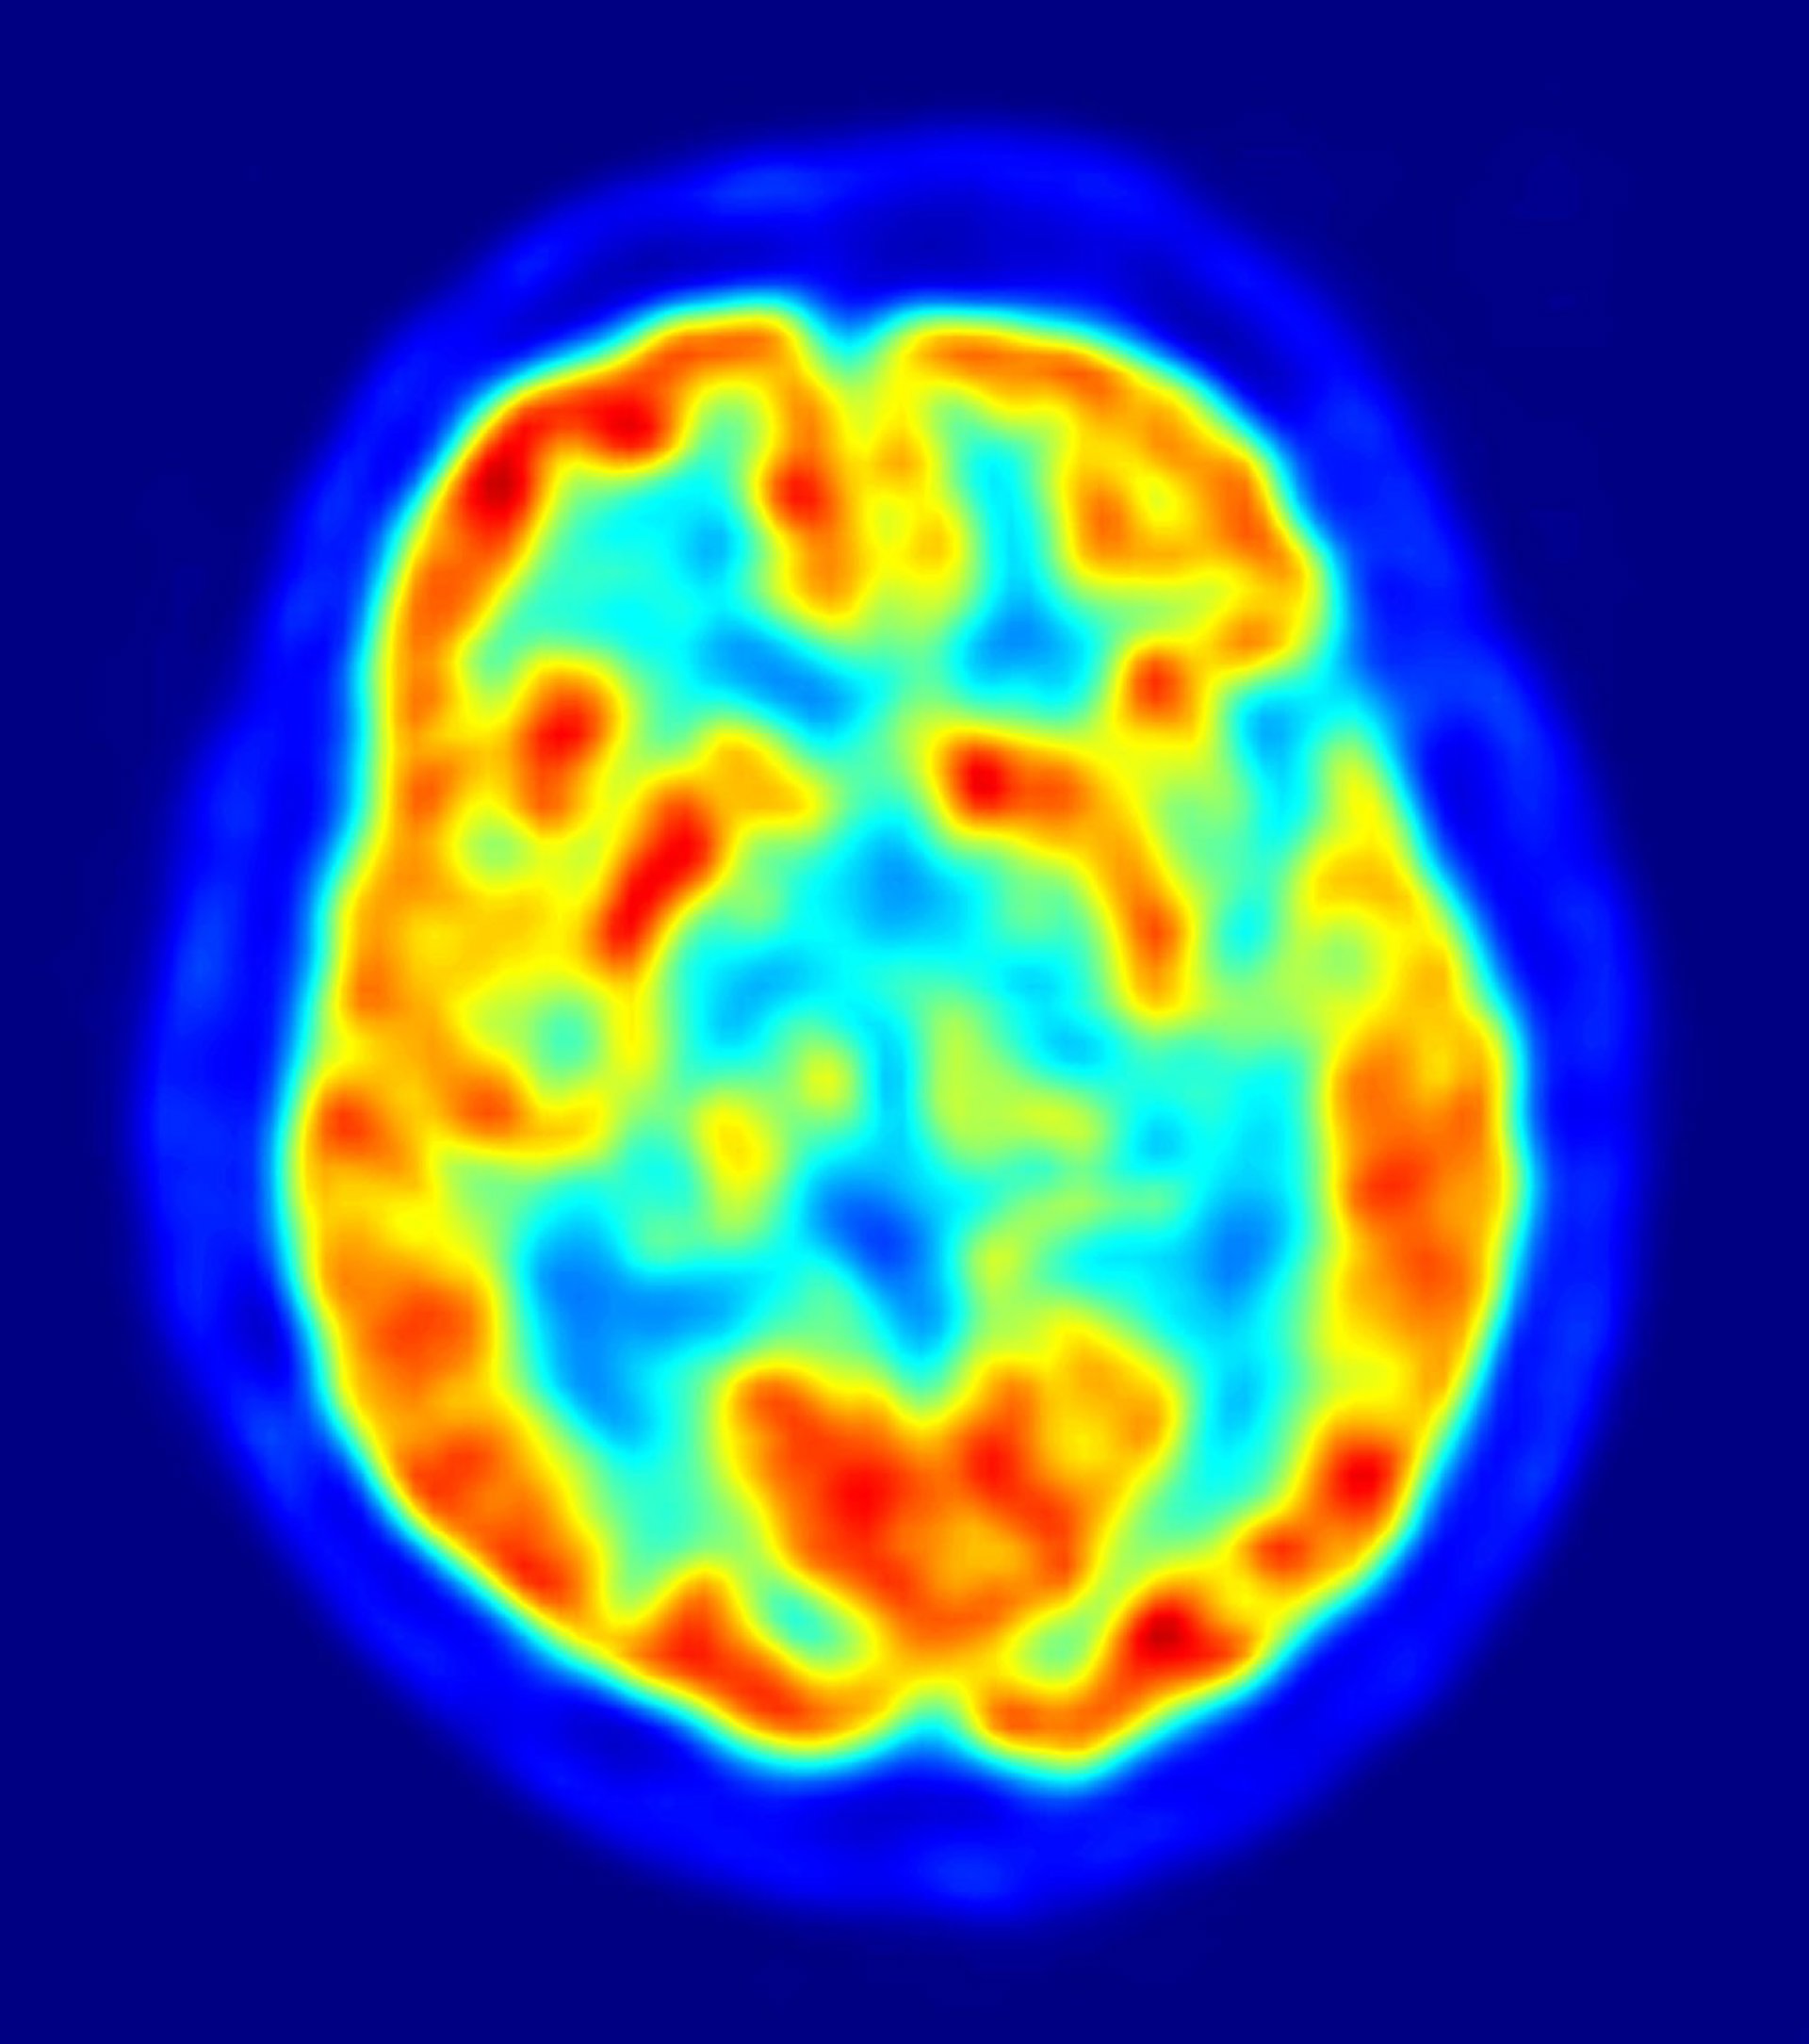

Un grupo multiinstitucional de investigadores ha encontrado nuevas proteínas candidatas para enfermedades de trastornos neurodegenerativos. En la revista 'Nature', James Shorter, profesor asistente de Bioquímica y Biofísica en la Escuela Perelman de la Escuela de Medicina de la Universidad de Pensilvania (Estados Unidos); Paul Taylor, del Hospital de Investigación Infantil St. Jude, y sus colegas describen que mutaciones en los priones como segmentos de dos proteínas de unión al ARN se asocian con un trastorno hereditario poco común que afecta a la degeneración del músculo, el cerebro, neuronas motoras y el hueso (llamado proteinopatía multisistémica) y un caso de la forma familiar de la esclerosislateral amiotrófica (ELA).

La ELA o enfermedad de Lou Gehrig es una enfermedad neurodegenerativa universalmente fatal. Estudios anteriores encontraron que mutaciones en dos proteínas de unión al ARNT, TDP-43 y FUS, causan algunas formas de esclerosis lateral amiotrófica, pero se sospechaba que había más proteínas que producían otras formas de la enfermedad. TDP-43 y FUS reguna cómo el código genético se traduce para el ensamblaje de las proteínas.

El nuevo estudio describe cómo las proteínas hnRNPA1 y hnRNPA2B1 mutan y provocan casos familiares de la enfermedad cerebral. Las mutaciones en hnRNPA1 y hnRNPA2B1 estuvieron presentes en dos familias con una degeneración hereditaria muy poco frecuente que afecta a los músculos, el cerebro, las neuronas motoras y hueso y otro de una persona con ELA familiar.